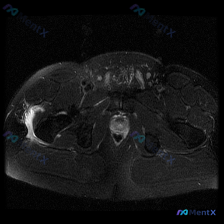

这是一份骨盆水平的轴位T2加权MRI扫描,涵盖髋关节、股骨近端、盆腔底部及周边软组织结构,核心异常在右侧区域:

- 核心异常发现:右侧股骨大转子外侧及前方,可见大片明显的T2高信号影,呈新月形/梭形包裹特征,位于股骨大转子外侧与臀中肌/臀小肌附着点之间,提示局部液体积聚或严重炎症水肿。

- 对称性对比:左侧对应部位软组织层次清晰,信号均匀,未见类似异常高信号,肌腱结构显示正常。

- 其他结构情况:双侧股骨头、股骨颈、髋臼形态基本正常,无明显骨质塌陷或破坏,骨髓腔信号无异常;盆腔内膀胱、直肠未见明显占位;右侧深部肌肉、坐骨神经周围未见明显异常水肿或移位。